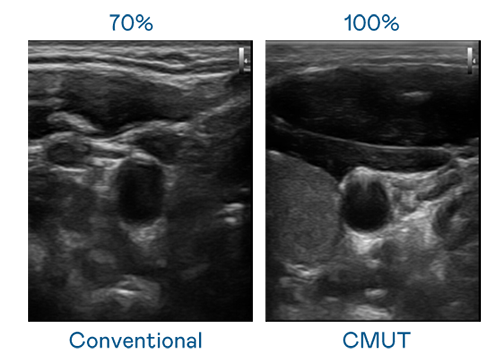

CMUT 技術是一種用電容式微機電元件來產生超音波訊號的技術。與傳統 PZT 壓電式技術相比,CMUT 頻寬增加 30%,更寬頻的超音波訊號讓影像解析度大幅提升,是實現高影像品質醫療超音波掃描、促進精準醫療發展的關鍵技術。

超音波影像的解析度高低,首先取決於探頭能發出的訊號頻寬。太阳集团7237 CMUT 可提供高清晰的超音波訊號,提供高頻寬、高靈敏度、影像紋理細節更高的超音波影像,協助醫護人員縮短影像判讀時間及利用精準的醫療影像進行診斷。